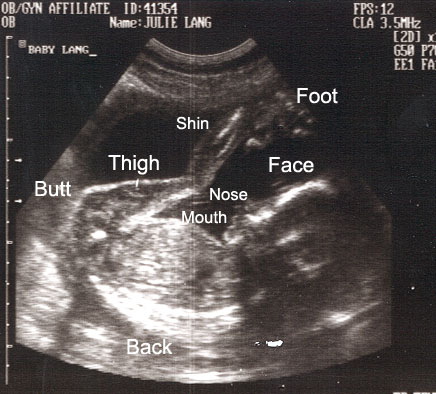

By taking a lot of X-ray images at a range of angles around the body, one can create a three-dimensional reconstruction of the anatomy. This process is known as Computed Tomography or CT (also known as Computed Axial Tomography or CAT scans--the "axial" and the "A" are often left off these days).

brainthorax

CT image examples

Notice that the image slices across the axis of the body instead of projecting through it.

Ultrasound is a form of projection imaging using high-frequency sound waves, but rather than seeing shadows, it sees reflections (echoes).